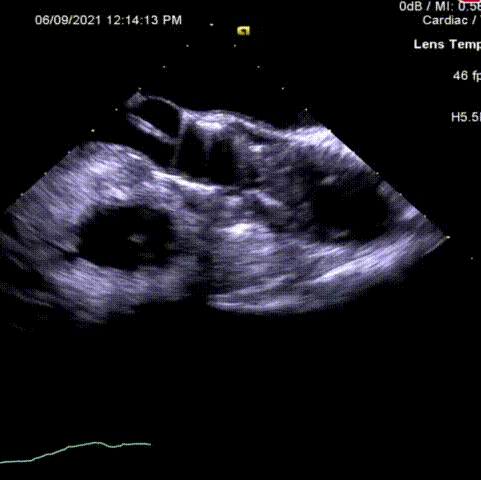

术后压差从52mmHg降至12mmHg

超声显示瓣膜位置及开闭形态良好。长轴及短轴多普勒结果显示均无瓣周漏,血流动力学优异